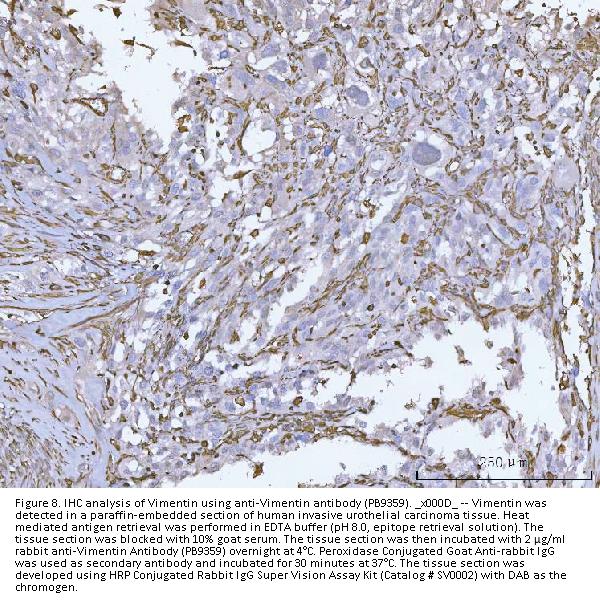

Immunohistochemistry (Paraffin-embedded Section), 0.5-1μg/ml, Human, Mouse, Rat

Cancer, Cell Type Marker, Cytoskeleton, Cytoskeleton/ECM, Developmental Biology, Intermediate Filaments, Intracellular, Lineage Markers, Lineage Specification, Neural Stem Cells, Neurogenesis, Neurology Process, Neuroscience, Signal Transduction, Stem Cells, Tumor Biomarkers

Boster Bio Anti-Vimentin Antibody Picoband® catalog # PB9359. Tested in IF, IHC, WB applications. This antibody reacts with Human, Mouse, Rat. The brand Picoband indicates this is a premium antibody that guarantees superior quality, high affinity, and strong signals with minimal background in Western blot applications. Only our best-performing antibodies are designated as Picoband, ensuring unmatched performance.